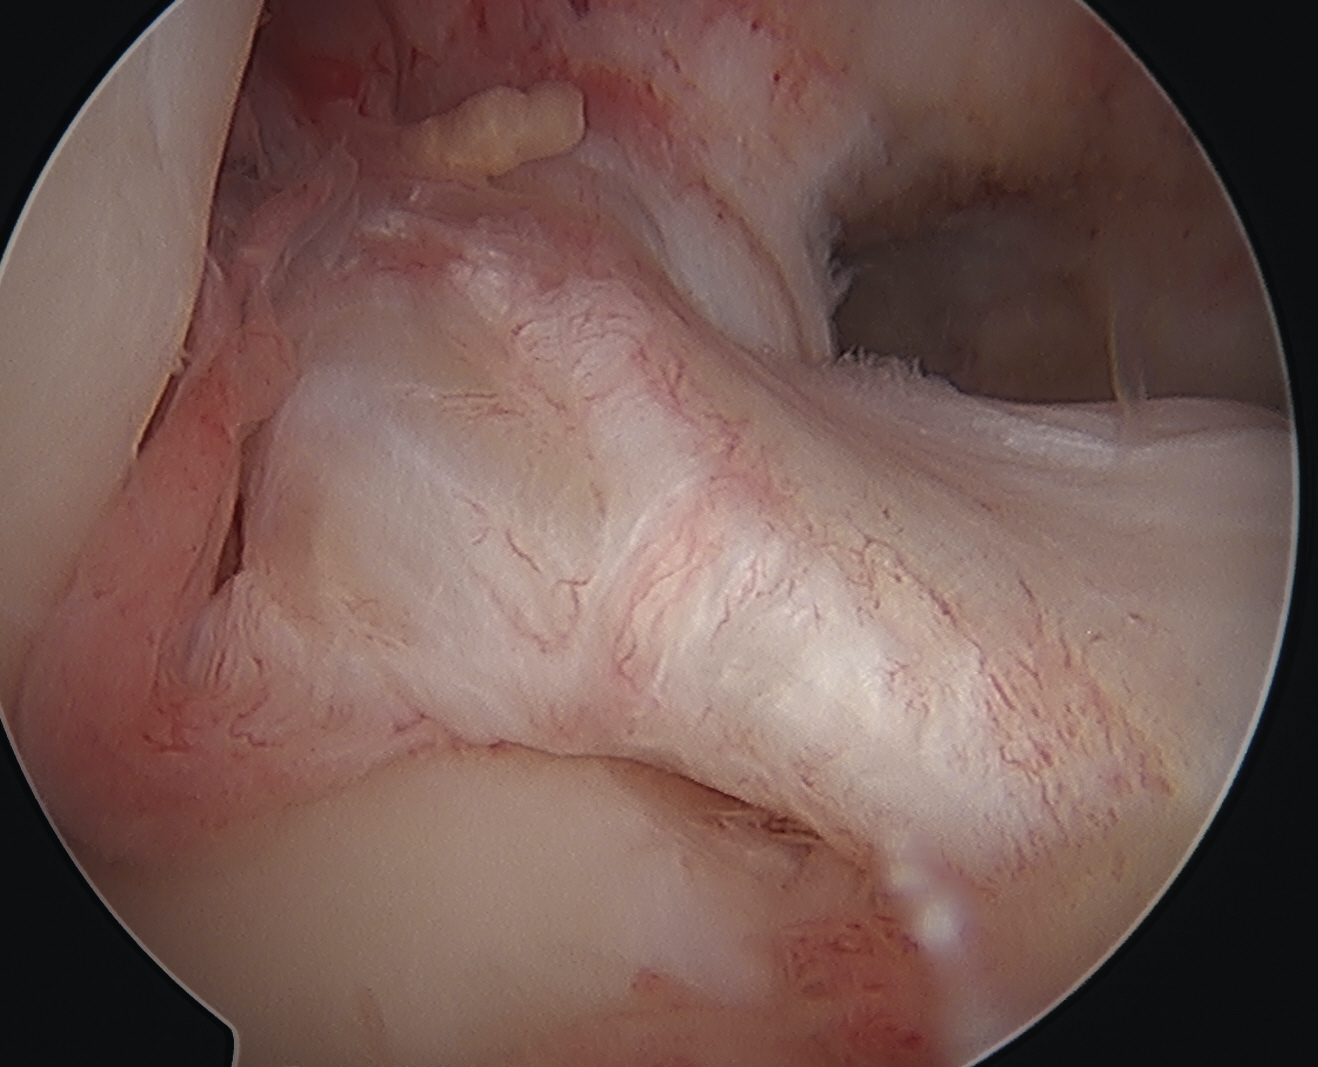

Arthroscopy

May miss tear as is extra-synovial

Chronic PCL tear from femur

Acute PCL femoral avulsion

Apparent ACL laxity due to PCL tear and posterior tibial sag; ACL tension restored with anterior drawer